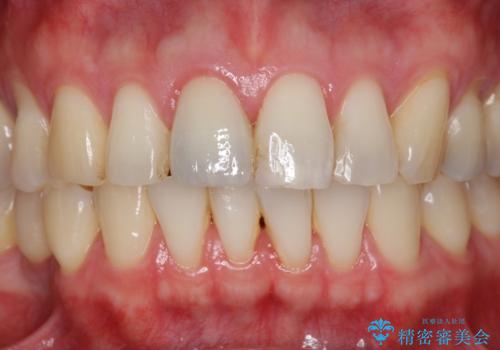

前歯の変色を改善 オールセラミック治療

感染の疑われる根管内に対し再度根管治療を行い、セラミッククラウンを作製することで審美性の回復します。

目立つ前歯の審美性が改善したことで見た目を気にせず笑えるようになった。との嬉しい感想をいただくことができました。